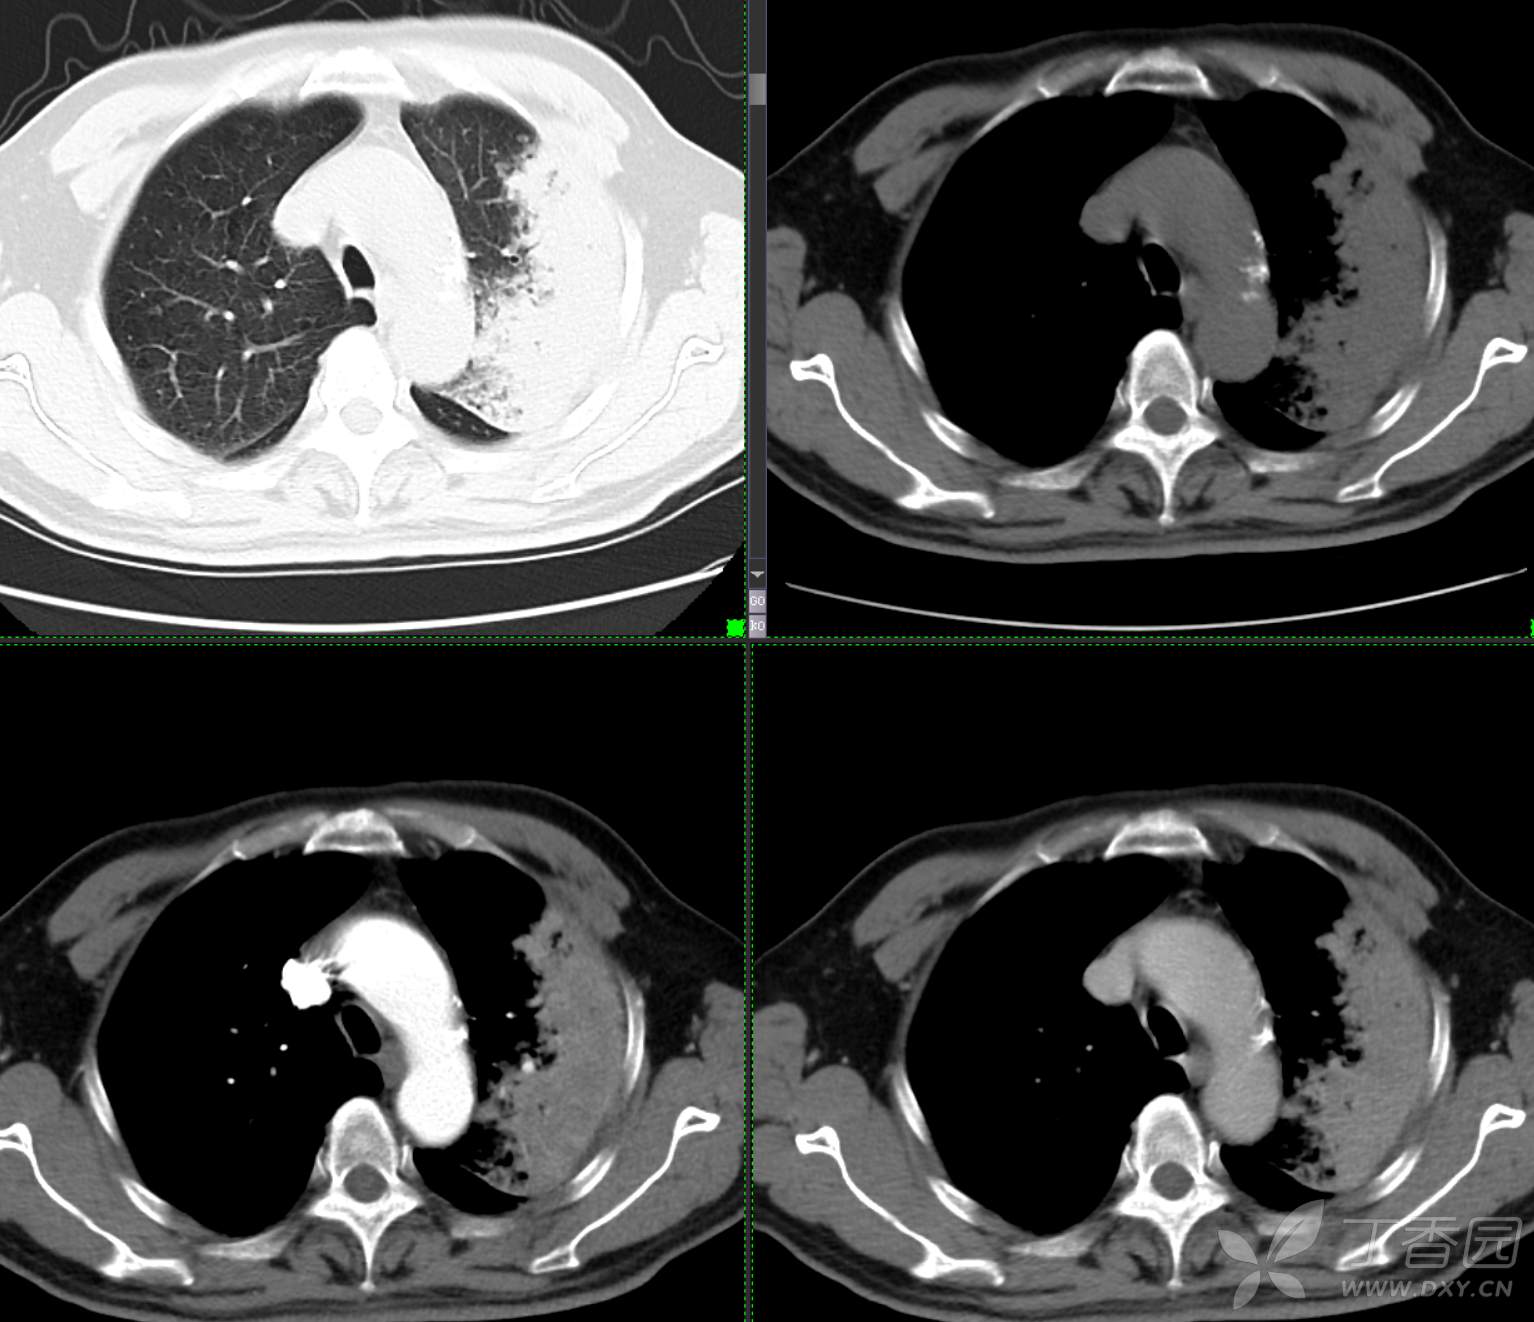

胸部29:大叶性病变,有征象,有特点,你的诊断?

患者性别:男

患者年龄:65

主诉:咳嗽2月余

简要病史:患者2月余前无明显诱因下出现咳嗽,干咳为主,夜间加重,伴咳痰,量中等,白粘痰为主,无明显胸闷气促,无恶心呕吐,无鼻后滴液,无发热畏寒,无鼻塞流涕不话,患者至当地医院就诊,考虑肺部感染,住院治疗,先后予“哌拉西林他挫巴坦针、莫西沙星针、美罗培南针、亚胺培南针、利奈唑胺片”抗感染治疗,患者咳嗽症状稍有好转,但仍存,为进一步诊治至我院门诊,现为进一步诊治,拟“肺部阴影、肺部感染”收治入院。